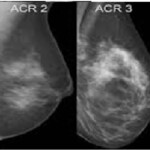

Γιὰ πολλὲς γυναῖκες, ἡ διάγνωση «καρκῖνος τοῦ μαστοῦ» κρέμεται ὡς δαμόκλειος σπάθη ἐπάνω ἀπὸ τὸ κεφάλι τους, εἰδικῶς ὅταν ἡ μητέρα ἢ ἡ αδελφὴ εἶχε ἤδη καρκῖνο τοῦ μαστοῦ, ἢ ἀκόμη ἀπεβίωσε ἐξ αἰτίας του. Μία στὶς ἑπτὰ γυναῖκες θ’ ἀναπτύξουν καρκῖνο τοῦ μαστοῦ κατὰ τὴν διάρκεια τῆς ζωῆς των, ἐξ αὐτῶν δὲ τὸ 80% σὲ ἠλικίες > 45 ἐτῶν. Ἐλπιδοφόρο μήνυμα ὅμως εἶναι, ὅτι ἡ θνησιμότητα τοῦ καρκίνου αὐτοῦ περιορίσθηκε σήμερα στὸ 10% τῶν προσβεβλημένων γυναικῶν χάρις σὴν συνεχῆ καμπάνια γιὰ προληπτικὸ ἔλεγχο. Γιὰ τὴν καλύτερη συνεργασία μεταξὺ τῶν ἐργαστηριακῶν καὶ τῶν κλινικῶν γιατρῶν, καθὼς ἐπίσης γιὰ τὸ ὅσον τὸ δυνατὸν μεγαλύτερο ὄφελος τῶν ἀσθενῶν (οἱ ὁποῖοι πρέπει νὰ γνωρίζουν, ὅ, τι ἡ συχνότητα τοῦ καρκίνου τοῦ μαστοῦ αὐξάνεται σὲ ὅλο καὶ μικρότερες ἡλικίες, ἐνίοτε δὲ καὶ κάτω τῶν 30 ἐτῶν) , τὰ ἀποτελέσματα τῆς μαστογραφίας ἔχουν κωδικοποιηθεῖ. Ἡ κωδικοποίηση αὐτὴ ξεκίνησε ἀπὸ τὸ American College of Radiology (ACR), τὸ ὁποῖο εἰσήγαγε τὸ Breast Imaging Reporting and Data System μὲ τὸν κωδικό BIRADS , ποὺ ἀναφέρεται στὰ ἀκτινολογικὰ, ὑπερηχογραφικὰ κριτήρια παθολογίας, ὅπως ἐπίσης καὶ στὰ ἀντίστοιχα τῆς μαγνητικῆς τομογραφίας. Ἡ κωδικοποίηση ACR ἀναφέρεται στὶς κατηγορίες πυκνότητος τῶν μαστῶν στὴν μαστογραφία. Καὶ οἱ δύο κωδικοποιήσεις παραπέμπουν στὸ ποιὰ περαιτέρω βήματα ἀπαιτοῦνται, προκειμένου νὰ τεθεῖ ὁριστικὴ διάγνωση κατὰ περίπτωση.Ἡ κωδικοποίηση αὐτὴ ἔγινε δεκτὴ καὶ καθιερώθηκε πλέον σ’ ὅλες τὶς χῶρες τῆς Εὐρωπαϊκῆς Ἑνώσεως, Αὐστραλίας, Ἰαπωνίας, ΗΠΑ, Καναδᾶ κ. ἄ. Οἱ ἀσθενεῖς βλέπουν πλέον στὶς ἐκθέσεις τῶν ἀκτινολόγων τοὺς κωδικοὺς BIRADS, ACR καὶ πρέπει νὰ ἐξοικειωθοῦν μ’ αὐτούς, διότι στὸ τέλος –τέλος παραπέμπουν στὸ ἐρώτημα ποὺ συχνὰ δεχόμεθα οἱ ἀκτινολόγοι ἀπὸ τὶς ἀσθενεῖς μας: «κάθε πότε πρέπει νὰ κάνω μαστογραφία γιατρέ; χρειάζεται νὰ κάνω κάτι παραπάνω;».